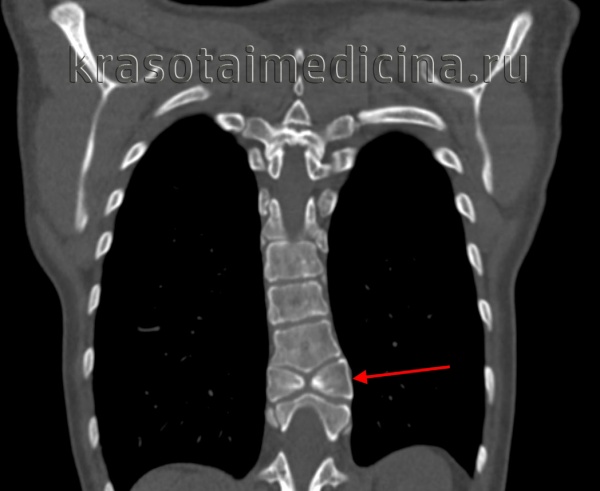

в) Расщепление спинного мозга. Термин «расщепление спинного мозга» (РСМ) был предложен Pang и Dias; могут быть выделены два типа. Тип I расщепления спинного мозга (РСМ) относится к наличию двух геми-корд, имеющих две отдельные твердые мозговые оболочки, разделенные срединным костным или соединительнотканным шипом. Тип II расщепления спинного мозга (РСМ) описывает две гемикорды, разделенные волокнистой перегородкой по средней линии в пределах одной твердой мозговой оболочки. Альтернативная терминология «диастематомиелия», обозначающая расщепление спинного мозга на две половины, или «дипломиелия», описывающая полное дублирование сегментов спинного мозга, сложнее для оценки. Существуют различные теории патогенеза, но большинство из них относятся к раннему нарушению слияния хордальных зачатков в одну хорду в течение третьей недели беременности. Нарушение слияния хорды дает две гемикорды.

В последствие перемещенная соматическая ткань может привести к неправильной сегментации позвоночника. Существуют многочисленные связанные врожденные аномалии, такие как ЛМЦ, липома терминальной нити или дермальный синус. У многих детей с расщеплением спинного мозга (РСМ) при рождении симптомы не выявляются. Могут присутствовать кожные стигмы. Гипертрихоз особенно сильно коррелирует с расщеплением спинного мозга (РСМ) (50%). Дисфункция мочевыводящих путей описана у 75% обследованных пациентов.

Хирургическая стратегия. С расщеплением спинного мозга (РСМ) тесно связаны сопутствующие врожденные аномалии, которые могут способствовать ФСМ, поэтому необходимо предоперационное изображение всего позвоночника на МРТ. При разработке стратегии лечения следует учитывать все аспекты, которые могут способствовать ФСМ. В частности, должно быть исключено наличие липомы терминальной нити. Аномальные формы позвонков и искривление позвоночника могут осложнить идентификацию позвоночного канала. Во-первых, дуральный мешок должен быть визуализирован. В случае РСМ типа I срединная костная шпора должна быть удалена. Впоследствии, дуральные мешки должны быть открыты для того, чтобы выполнить диссекцию.